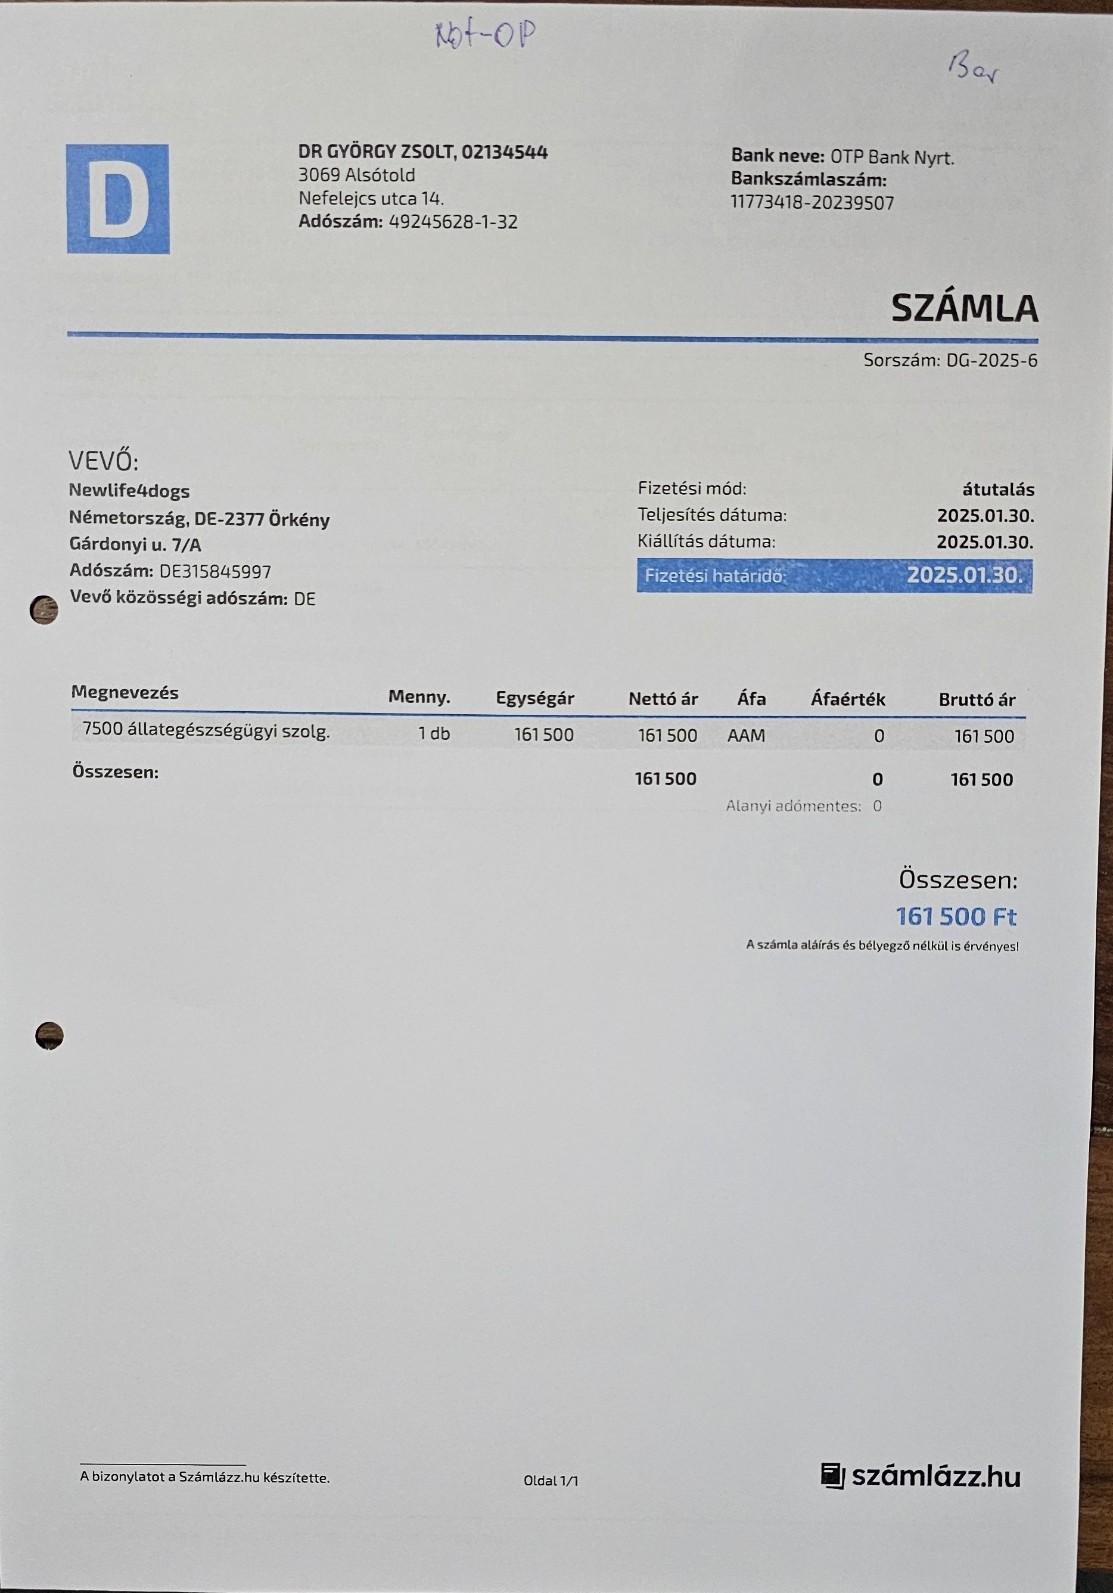

Nachdem die kleine Stella nach mehr als einer Woche die Klinik verlassen durfte, Mussten erneut einige unserer Neuzugänge dringende Not-OP´s und stationäre Aufnahme +ber sich ergehen lassen. So auch der kleine Sidney, den wir schwer verletzt mit gebrochenem Hinterbeinchen auf der Strasse in Nordungarn fanden. Sofortige Untersuchungen, Rüntgenaufnahmen und unverz+gliche Notoperation war erforderlich. Die Operation hat der kleine Mann gut überstanden. Nun benütigt er weitere Medikamente und Vitaminprodukte, damit er einen guten Heilungsprozess durchlaufen kann. Ebenso benütigt er 6 Wochen Zwingerruhe und Physiotherapie.

Auch unser lieber Oskar musste heute notfallmäßig in die Tierklinik. Aus derzeit noch unerklärlichen Gründen kann oskar sich nicht mehr auf seinen Hinterbeinen halten. Natürlich brachten wir ihn sofort in die Klinik. dort wurde er stationär aufgenommen. Nun ist eine MR untersuchung erforderlich, um die Ursache f+r die plützlichen Lähmungserscheinungen zu finden. Auch in der zweiten hälfte des Monats mussten wir wieder hohe Klinikkosten und Tierarztkosten bewältigen. Wir wären extrem erleichtert und dankbar wenn uns der ein oder andere hierbei unterst#tzen würde.